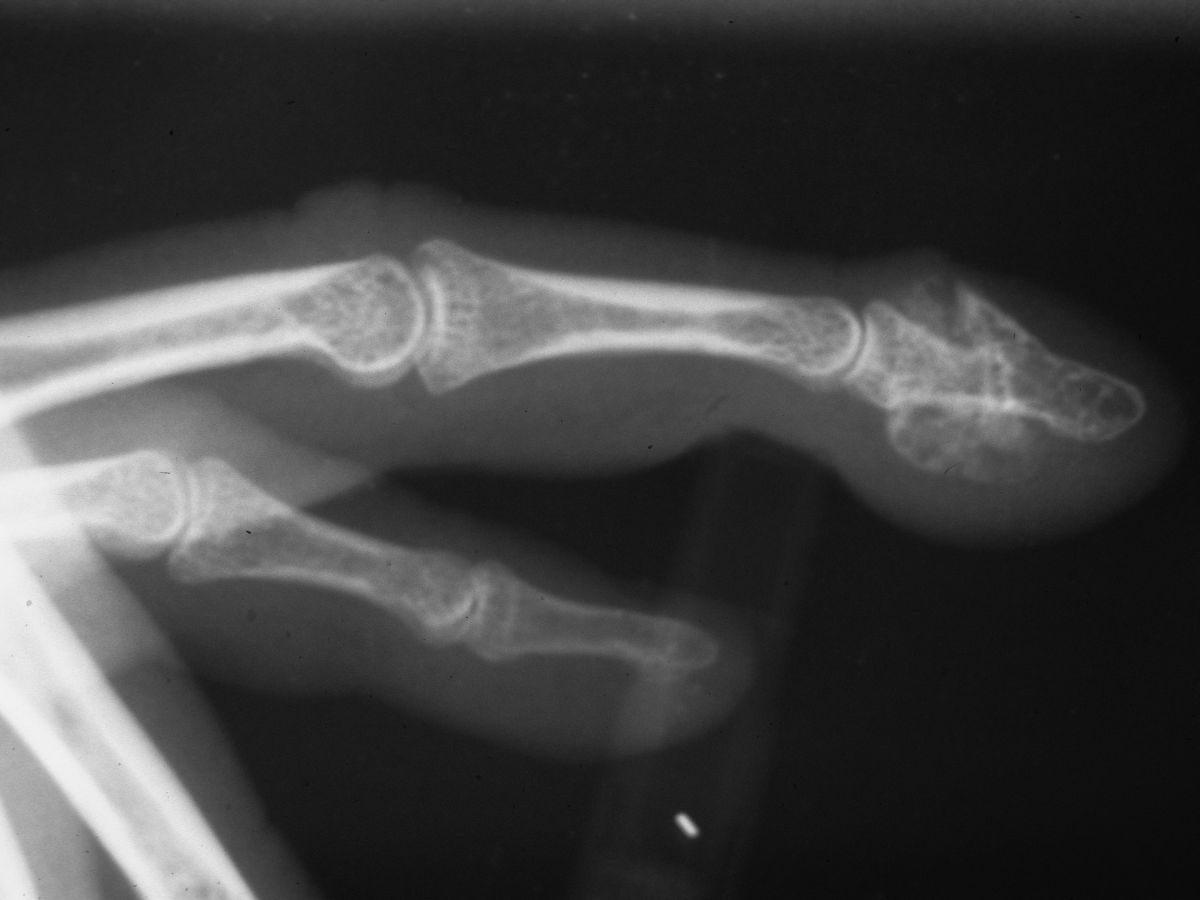

| Case 1. This young woman presented with a painless distal phalanx and nailbed deformity which developed slowly during her teens |

| Plain Xrays show continuity of abnormal bone the with the medullary bone of the distal phalanx. |